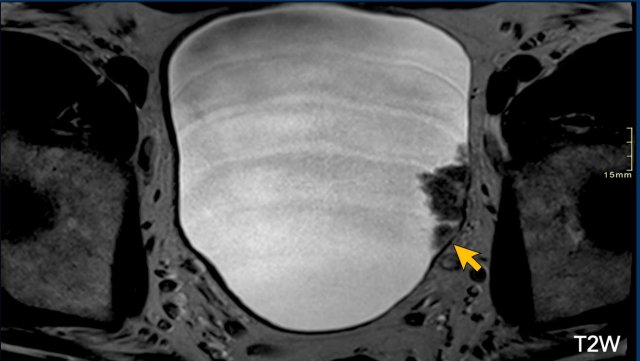

Image

There is a sessile tumor on the lateral left bladder wall.

Since there is no tumor stalk and inner layer, but there is also no clear interruption of the muscular layer, this should be scored as T2W: 3.

Continue...

Next step is to study the DCE and diffusion images to differentiate between VI-RADS 2, 3 and 4.